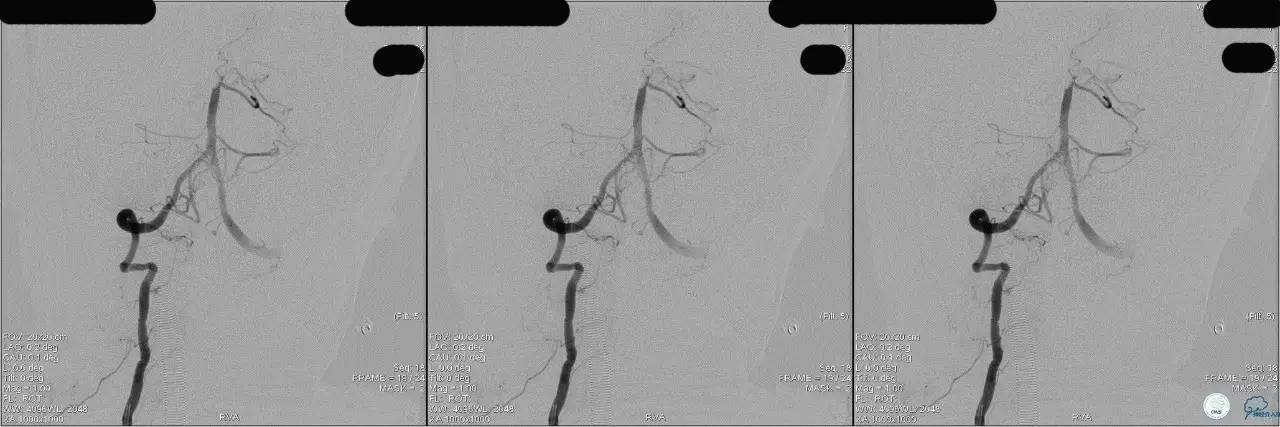

》DSA资料(左侧颈动脉)

》DSA资料(右侧颈动脉)

》DSA资料(左侧椎动脉)

》DSA资料(右侧椎动脉)

》DSA资料(前2次取栓,未取出,soli 4-20)